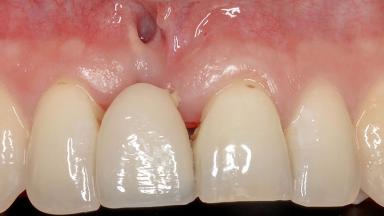

Soft-Tissue Augmentation Using a Porcine-Derived Collagen Matrix to Correct a Labial Soft-Tissue Defect Following Extraction of a Maxillary Incisor

In this case, Shakeel Shahdad employs a two-layer matrix to repair a soft-tissue defect in a post-extraction healed site prior to implant placement with simultaneous guided bone regeneration. This approach resulted in a gain of keratinized peri-implant mucosa with optimal shade and texture. Soft-tissue defects are often encountered prior to implant placement and may result in deficient attached keratinized mucosa, which unless corrected will yield less than ideal esthetic outcomes. The presence of keratinized mucosa has been proposed as one of the prognostic factors for the survival of dental implants (Adell and coworkers 1986) with reported greater reductions in gingival and plaque indices after increasing the width of keratinized mucosa by soft-tissue augmentation (Giannobile and coworkers 2018; Thoma and coworkers 2018).